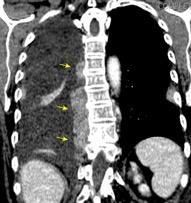

Tumor desmoide (“Fibromatosis agresiva”)

T1: Isointensos con músculos.

T2: Señal intermedia y de alta intensidad.

Presencia frecuente de áreas curvilíneas y lineales dentro de la lesión

Mansour J et al. Diagnostic and Imaging Approaches to Chest Wall Lesions. Radiographics 2022

Densidad similar al músculo con estriaciones internas de grasa